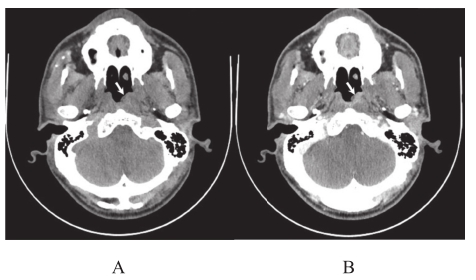

肿瘤浸润鼻咽顶后或侧壁,使鼻咽腔变形、狭窄,咽隐窝变浅、消失,鼻咽壁增厚或形成肿块向腔内突出,CT平扫呈软组织密度,增强后肿块呈中等程度强化(图2-3-1)。

图2-3-1 鼻咽癌CT表现

A—鼻咽部平扫CT;B—增强扫描。